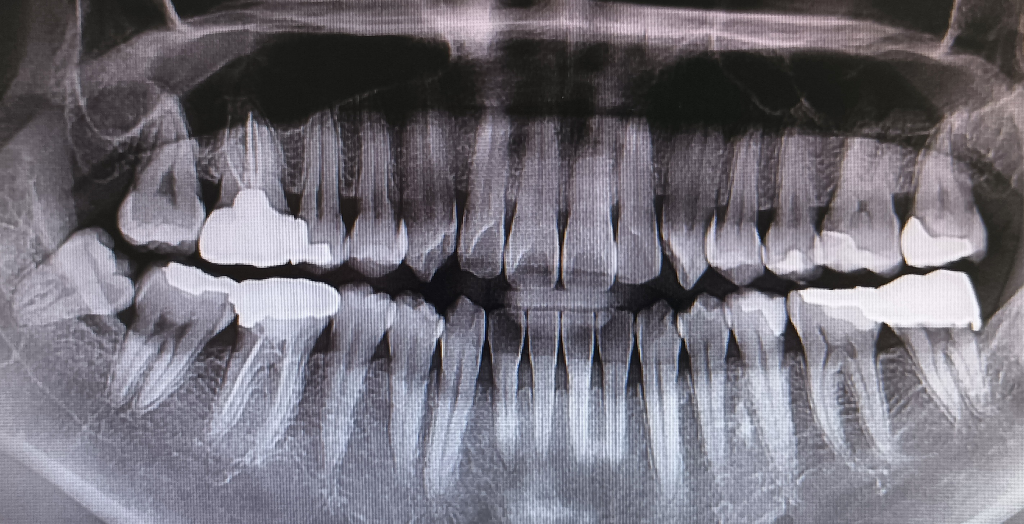

치주질환관련하여 질문합니다.(파노라마포함)

1. 30대 중반입니다. 치과에 가서 스케일링 받는데 잇몸이 나이에 비해서 많이 내려갔다고 합니다. 이정도면 어느정도 상태일까요?

2. 사랑니 바로 옆 어금니 잇몸이 많이 내려가서 이개부노출(?)로 나중에 문제가 될 수도 있다고 합니다. 안쪽으로 잇몸을 만져보면 다른쪽에 비해서 그 쪽 치아만 파인 것 같은데 이런 경우 조직유도재생술 같은 치료가 가능할까요? 아니면 다른 치료 방법이 있을까요?

3. 만약 조직유도재생술이 가능하다면 사랑니를 이용한 자가치아뼈 사용도 가능할까요?

1. 특별히 가장 문제가 되는 부분이 본인 기준으로 오른쪽 아래 사랑니 앞에 치아입니다. 사랑니에 의해서 치아에 충치도 생겼으나 잇몸도 상당히 많이 내려간 상태입니다.

사진으론 뼈상태만 볼수잇고, 임상적인 검사는 할수없기 때문에 정확히 알 순 없습니다.

뼈상태는 아주 나쁜편은 아니지만, 치근이개부병변이 있다면 좋진 않습니다.

하지만 현재 GTR이나 GBR을 할만큼 잇몸뼈가 나빠보이진 않습니다. 이점에 대해선 해당치과에서 자세히 상담을 받아보시기 바랍니다. 감사합니다.

1. 어금니 부위 일부 잇몸이 상대적으로 많이 내려가 있는 것으로 보이나 나머지 부분은 양호합니다.

2. 조직유도재생술이라는 술식을 어디서 들으셨는지는 모르나 치주질환으로 인한 골소실의 경우 골이식을 통해 회복하는 것이 가능합니다. 하지만, 성공여부는 사람마다 차이가 있습니다. 이식 및 재생을 위한 술식을 하지 않는 다면 잇몸 치료를 지속적으로 받으면서 병의 진행이 더 이뤄지지 않게 막는 것이 최선입니다.

3. 사랑니를 뽑아 골은행을 통해 자가 이식골로 사용하는 것이 가능합니다. 비용과 시간이 어느정도 소요되나 충분히 사용 가능한 것으로 알 고 있습니다.